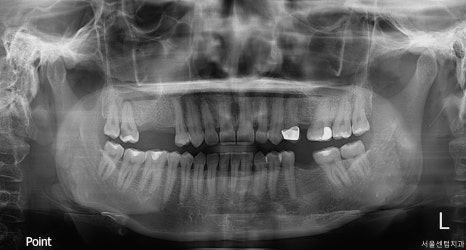

수술전 검사 및 골평가

정확한 진단을 위해서는 파노라마 촬영과

CBCT 촬영을 진행을 했는데요.

이 과정이 꼭 필수적인 이유는

육안으로 보이지 않는 뼈의 상태와

신경의 위치, 상악동까지의 거리 등을

정밀하게 파악 할 수 있기 때문입니다.

치료시작 전 전체 치아 사진